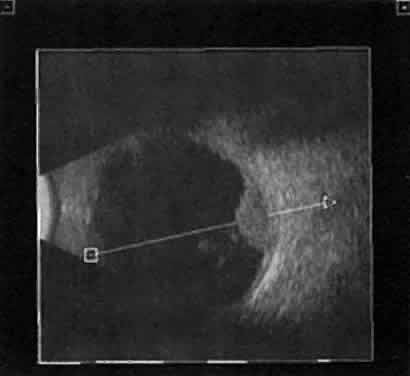

Recent improvements in computer technology and digital B-scan devices have permitted the development of tomographic (3D) static displays. The new devices, often called 3D ultrasound instruments, increase understanding of complex topographic information (Fig. 18). Sophisticated software permits measurements of captured images (linear, area, and volume) as well as surface renderings18,19 (Figs. 19 and 20). Kinetic (real-time) information is not yet available in 3D and continues to be obtained during kinetic B-scan examinations performed before 3D image capture.

Fig. 19. 3D tomographic ultrasonogram. Area and volume measurement tracings are possible using software, as seen in this outlined melanoma.

Fig. 20. 3D tomographic ultrasonogram: linear measurement of a melanoma height derived from tomographic B-scan.